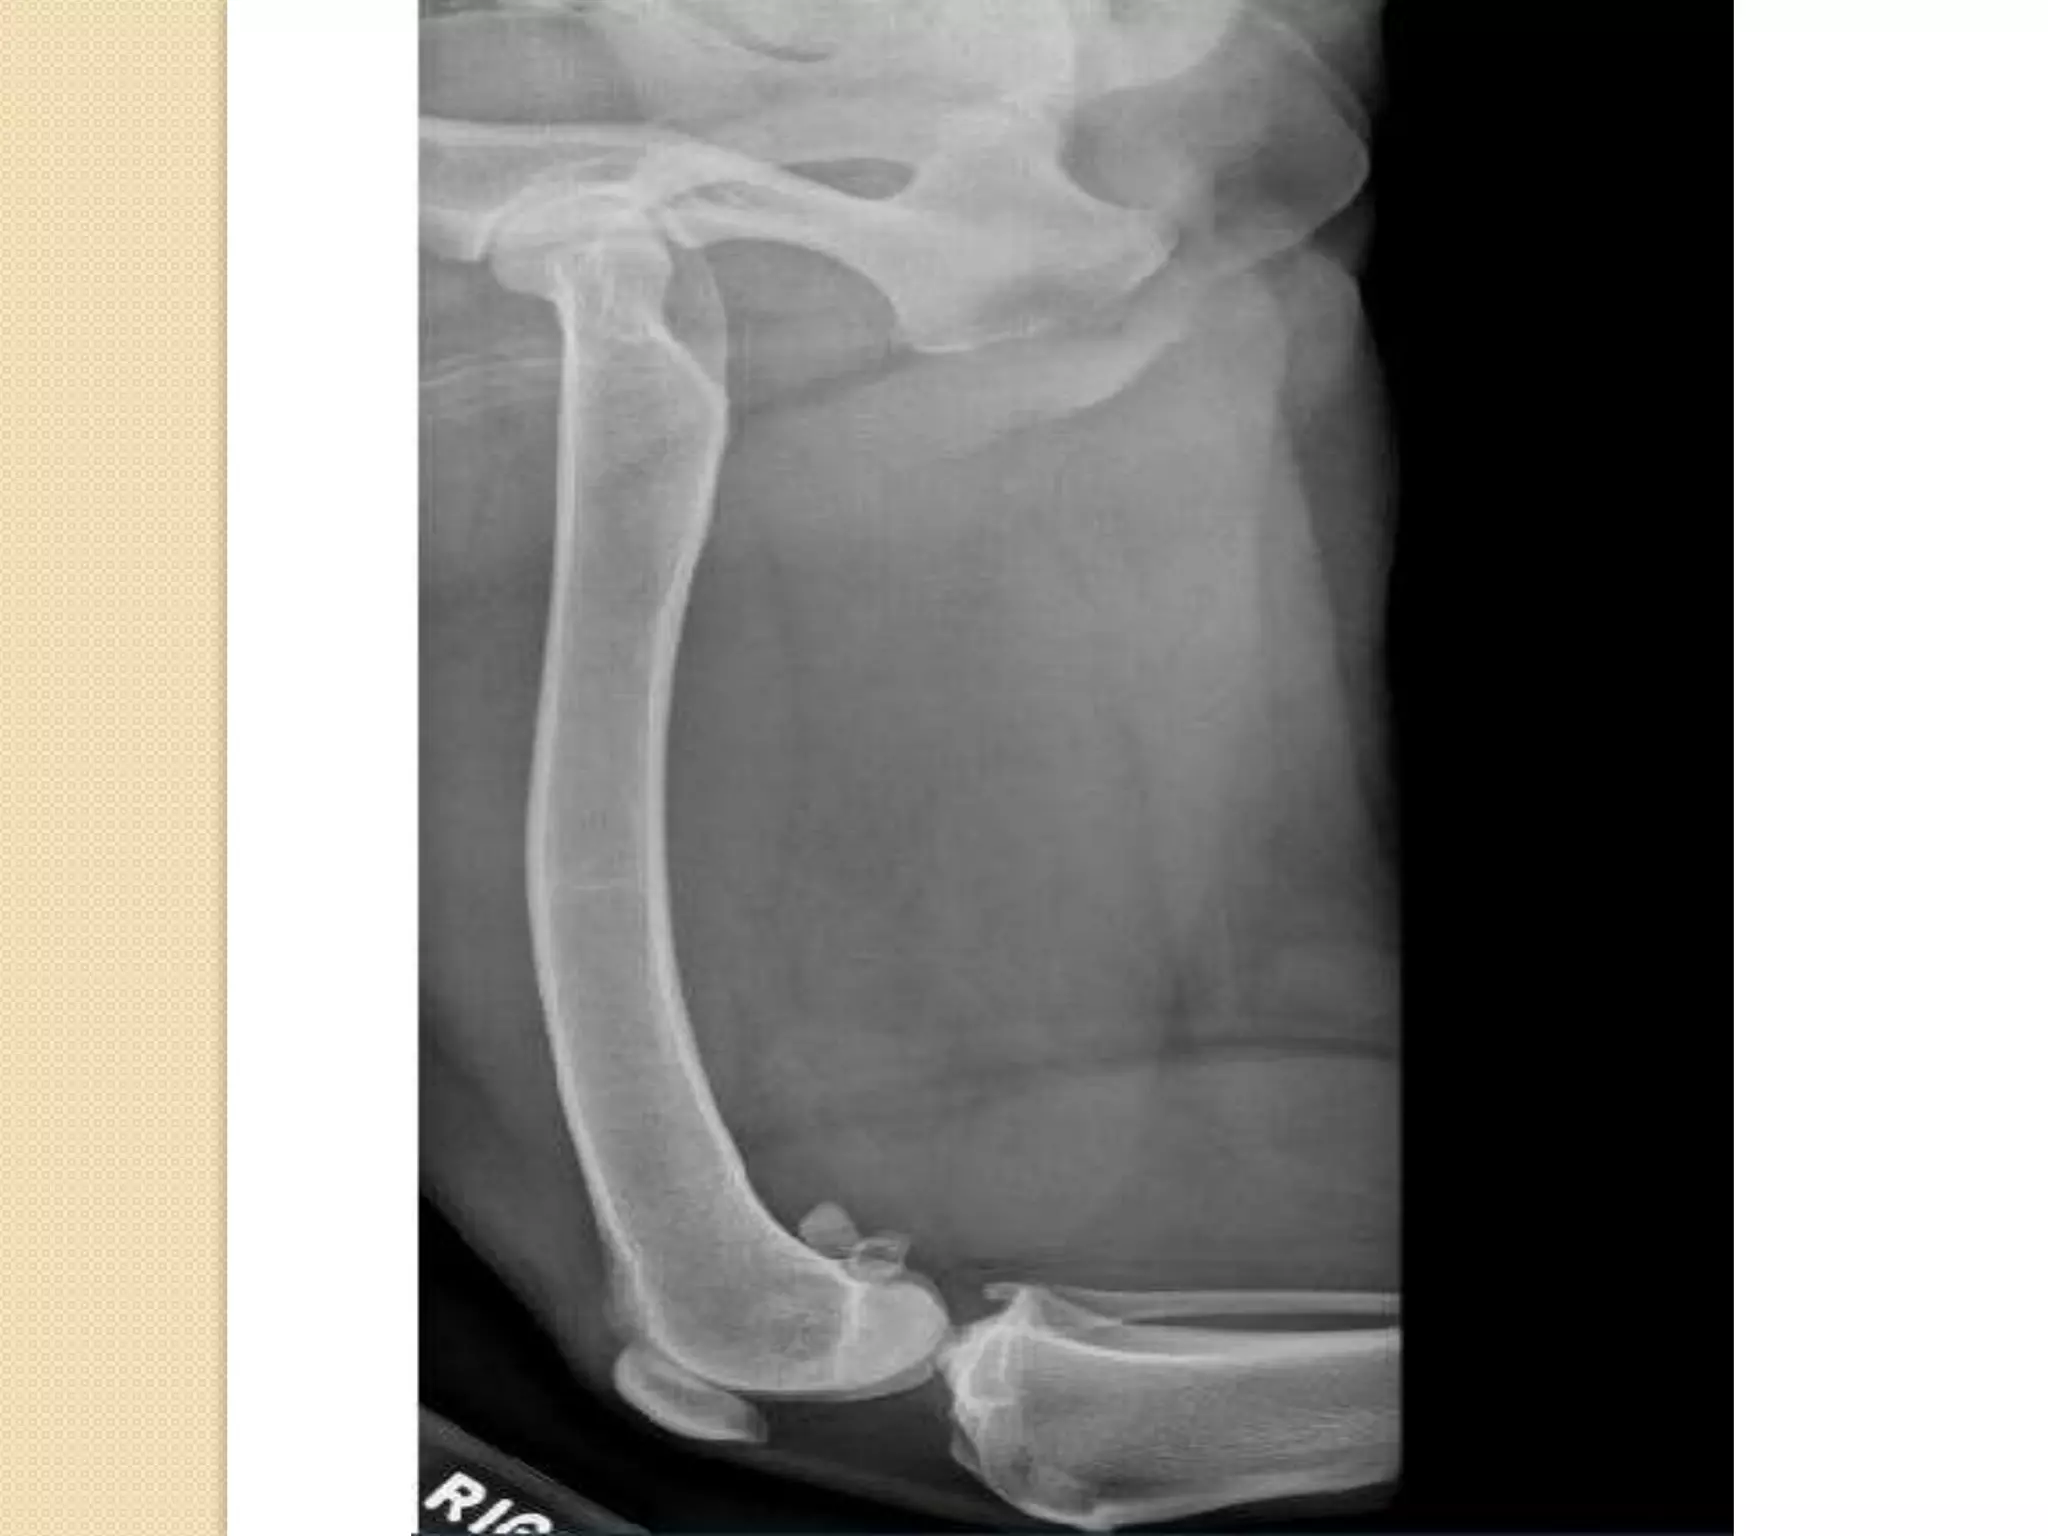

Femur :

It is a long bone which form the thigh

region.

The head of the femur form the hip joint

with the acetabulum of the os coxae .

The caudal surface characterized by 2

rough lines diverge proximally and distally

towards the extremities called linea

Aspera

The present of the supracondyloid facets.

Hip joint:

Hip joint is formed of the head of the femur

with the acetabulum of os coxae.

Femur : It isa long bone which form the thigh region. The head of the femur form the hip joint with the acetabulum of the os coxae . The caudal surface characterized by 2 rough lines diverge proximally and distally towards the extremities called linea Aspera The present of the supracondyloid facets.

Hip joint: Hip jointis formed of the head of the femur with the acetabulum of os coxae.